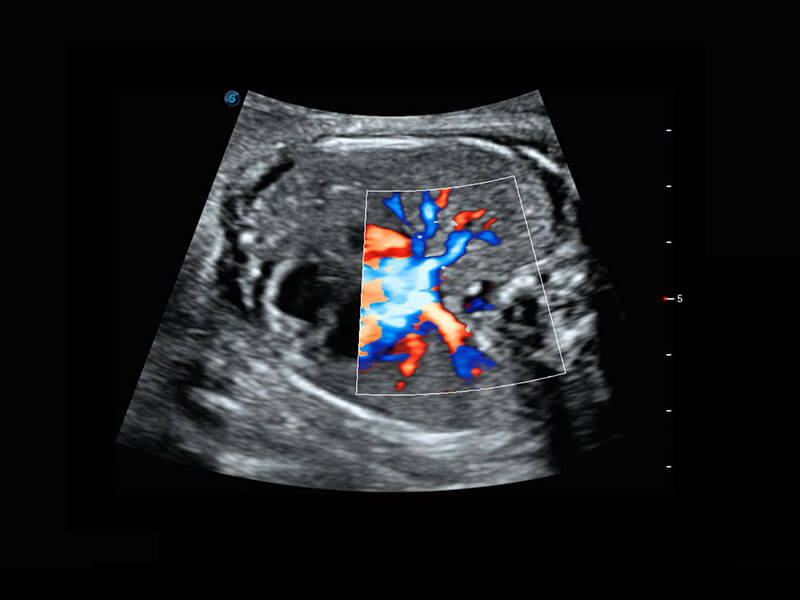

P60搭载一系列胎儿心脏成像技术,实现精细的胎儿心脏评估。

四腔切面

四腔心血流